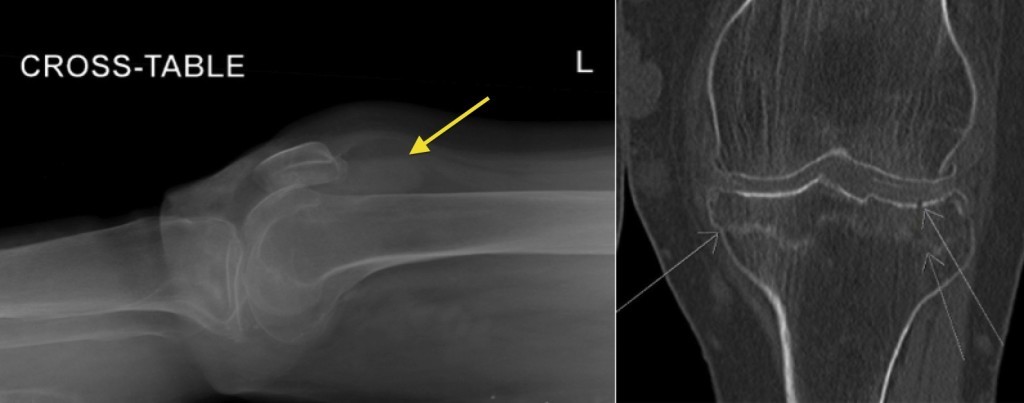

Describe the appearance of lipohaemarthrosis on x-ray

You will notice that there is a very straight line (arrow) at the superior aspect of the fluid, above which there is some low density material. This is fat floating on blood, and makes this a lipohaemarthrosis. The reason this is significant is that it means that there must be an underlying fracture, even if one cannot be seen on the radiograph (because the fat is actually marrow fat, and must have leaked into the joint through a fracture).